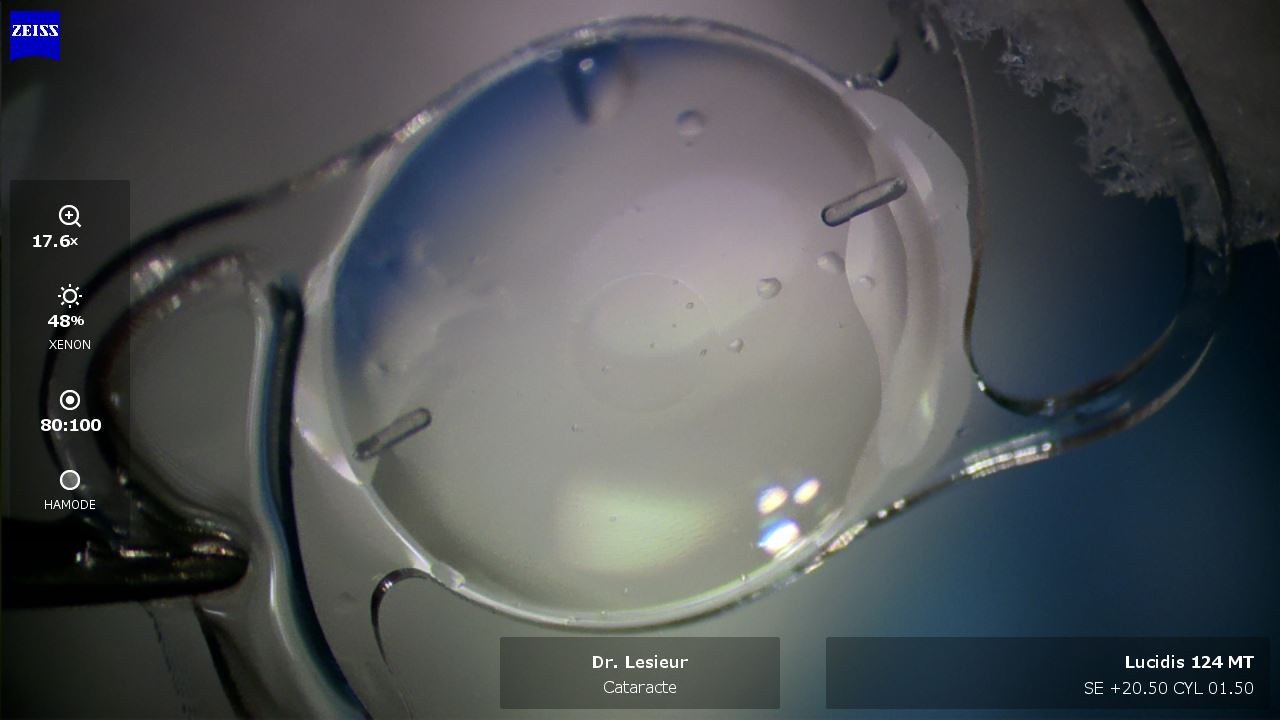

Retrait du cristallin

Le cristallin est fragmenté par ultrasons (phacoémulsification) puis aspiré délicatement. Cette technique éprouvée permet un retrait complet tout en préservant l'enveloppe du cristallin, qui servira de support à l'implant.

Pose de l'implant

L'implant intraoculaire, plié sur lui-même, est introduit par la micro-incision. Il se déploie à l'intérieur de l'œil et se positionne exactement à l'emplacement de l'ancien cristallin. Son centrage est vérifié avec précision.